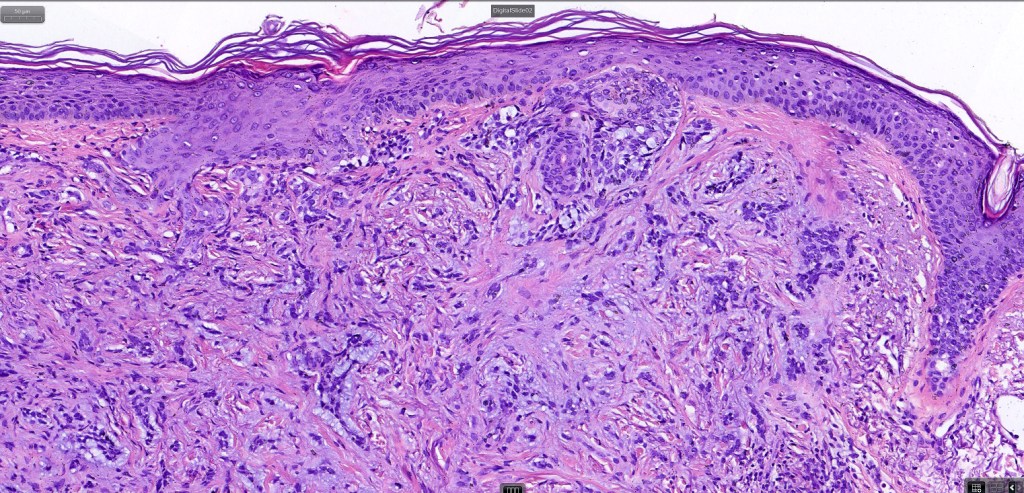

•The tumor commonly arises from the epidermis

•The epithelial component is composed of uniform small, basophilic devoid of desmosomes

•Peripheral palisading

•Retraction artifact with stromal mucin

•Pseudoglandular appearance

•A wide variety of histological variants are possible including nodular, nodulocystic, ulcerative, superficial, micronodular, infiltrating/infiltrative, keratotic, basosquamous, pigmented, morpheaform, keloidal, clear-cell, signet-ring cell & granular cell variants, BCC with monster cells, BCC with metaplastic features, BCC with matricial differentiation, basomelanocytic tumor (see separate blog), BCC with thickened basement membrane, BCC with carcinoid-like nuclear palisading & these are illustrated below